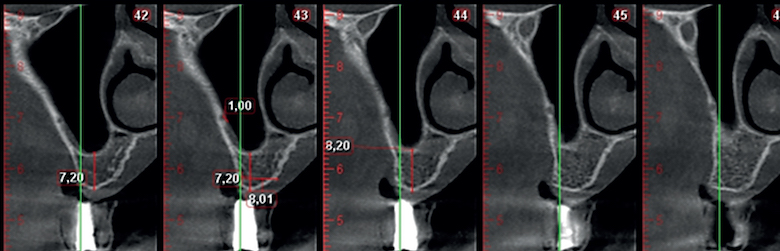

Fig. 3. Presencia del trayecto de la arteria.

El sangrado intraoperatorio resulta de dañar las ramas vasculares de la pared lateral del seno y de los tejidos blandos circundantes. También existe la posibilidad del sangrado desde una anastomosis extra ósea de la arteria alveolar superior posterior y la arteria infraorbitaria durante la elevación del colgajo y desde la arteria nasal lateral posterior. Para evitar una laceración de esta anastomosis y una vez se prevé la posibilidad de que exista una complicación hemorrágica, es prudente localizar la posición de la arteria en las imágenes de corte transversal del CBCT y luego utilizar un abordaje que respete la integridad de los tejidos.